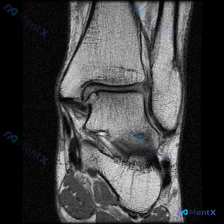

今天遇到一个挺有意思的病例,用户提示存在半月板异常,但只提供了单张膝关节MRI T1冠状位图像,整理一下分析思路分享给大家。 一、病例/影像基本信息 提供的单张膝关节MRI T1冠状位图像分析结果如下: 1. 骨骼结构:股骨远端、胫骨近端、腓骨近端轮廓清晰,骨髓信号正常,未见局灶性骨质破坏或异常信号...

刚整理了一个有意思的读片病例,临床和影像表现有点冲突,分享一下完整分析思路: 病例基础信息 这是一张膝关节MRI冠状位T1加权成像(T1WI),用户提示观察内容为「软骨异常」。 影像读片结果 先给大家说清楚各个结构的观察情况: 1. 骨骼结构:股骨远端、胫骨近端显示清晰,骨皮质低信号、骨髓腔中等信号...

看到这个病例很有代表性,整理了完整资料和分析思路分享给大家 病例与影像资料 本次评估的是单张膝关节MRI T1加权序列冠状位图像,临床提出问题:影像是否存在软骨异常? 对影像的详细评估结果如下: 1. 骨骼系统:股骨远端、胫骨近端骨皮质连续,无骨折,骨髓信号正常,无局灶低信号,无骨质破坏、囊变或骨赘...